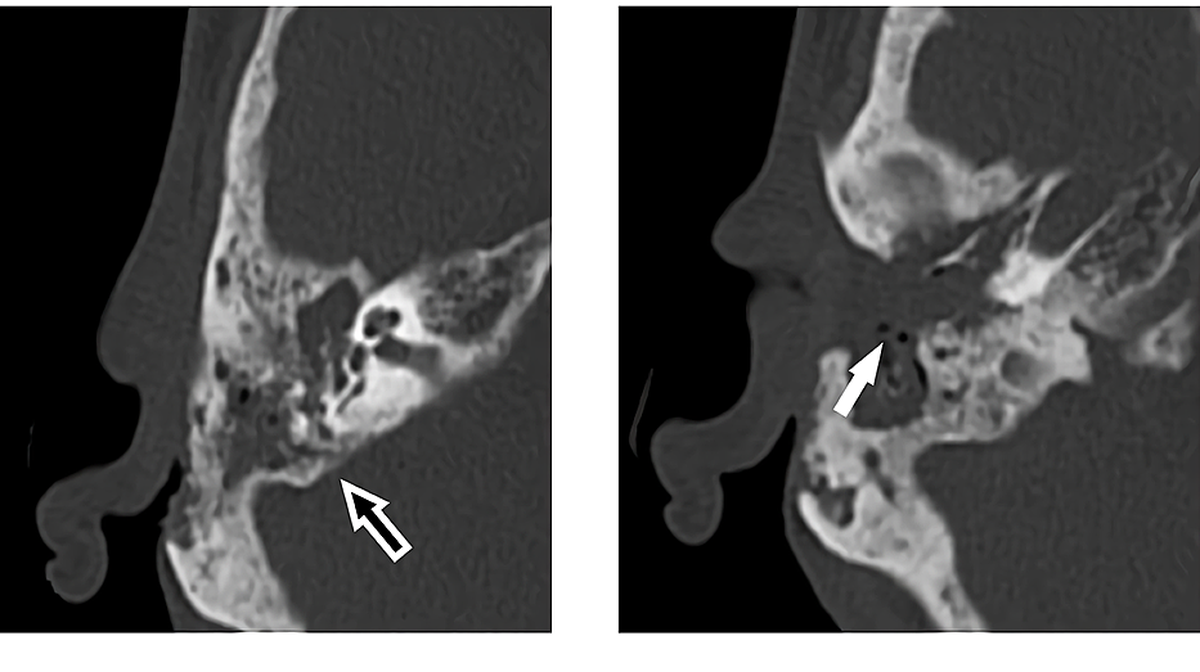

Jakarta – Seorang pasien berusia 65 tahun datang ke rumah sakit dengan masalah telinga. Setelah diperiksa, ternyata ada banyak belatung di telinganya.